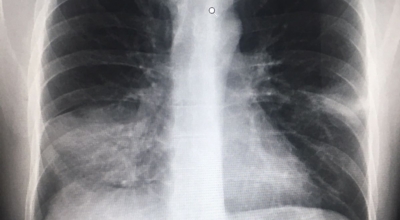

우리나라는 사망률 중 4위가 폐렴일 정도로 폐관련 질환은 위험도가 높다고 합니다. 우리의 몸 면역을 조절해주는 컨트롤 타워가 폐이기 때문에 그만큼 중요하며 호흡기 계통의 질병이 대부분 폐와 관련이 있기 때문에 폐 건강을 항상 챙겨두는 것이 좋습니다. 호흡기 건강, 폐 건강에 있어서는 비타민과 미네랄 그리고 항산화제가 풍부한 음식 몇 가지만 추가해도 체내의 염증을 줄이고 폐 기능을 개선하며 호흡기 건강을 증진시키는데 도움이 될 수 있습니다. 그럼 폐에 좋은 음식 10 가지를 알아보겠습니다.

폐이미지